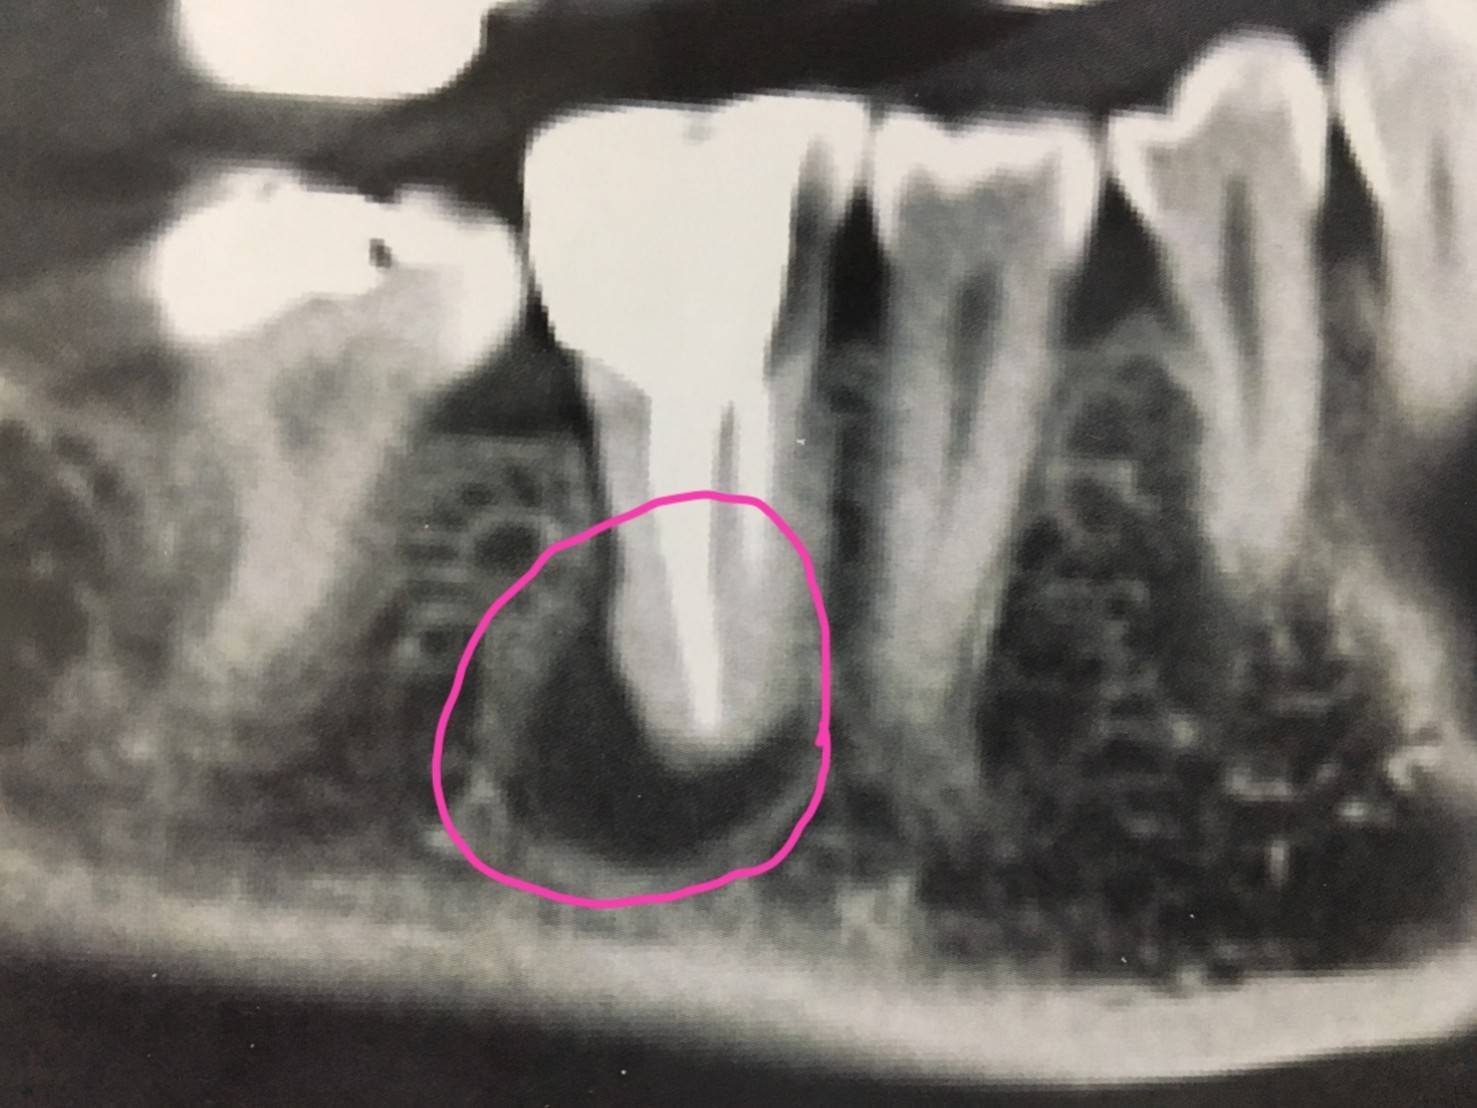

ครบ 2 เดือนวันนี้ ผลปรากฏว่า กระดูกสร้างขึ้นมาใหม่ได้ดีมาก จนเกือบเต็ม (ตามภาพที่ 2) สามารถใส่รากฟันเทียมได้เลย โดยไม่ต้องเติมผงกระดูก (ตามภาพที่ 3) ได้ประโยชน์ 2 ประการ

บริเวณสีดำในวงสีชมพู คือ กระดูกรองรับรากฟัน ที่เป็นโพรง เนื่องจากการรักษารากฟันไม่เป็นผลสำเร็จ จึงต้องถอนฟันซี่ดังกล่าวเมื่อปลาย มิย. 2560 เพื่อรอให้กระดูกรองรับรากฟัน มีการสร้างขึ้นมาใหม่ (ถมโพรงให้ตื้นขึ้นมา) เพื่อให้มีเนื้อที่กระดูกเพียงพอสำหรับการใส่รากฟันเทียม

วันนี้ครบ 2 เดือน คุณหมอเอ็กซเรย์ พบว่า โพรงกระดูกรองรับรากฟัน ตื้นขึ้นมาก เกือบเต็ม จึงจะผ่าเปิดดูกระดูกรองรับรากฟัน โดยมี 3 ทางเลือก